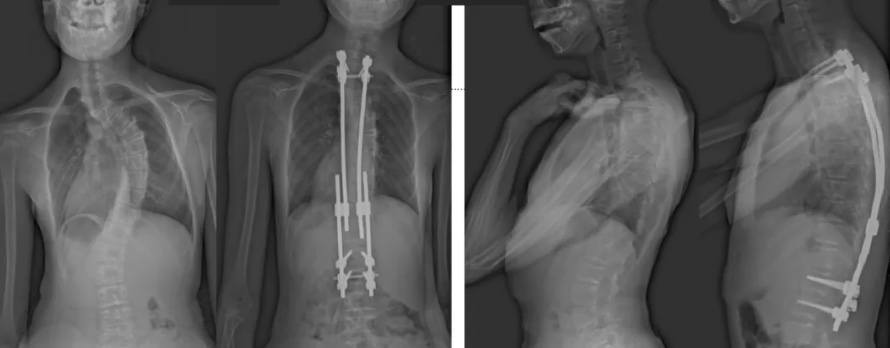

白玛的正位术前、术后对比图(左侧);侧位术前、术后对比图(右侧)

术后第二天,白玛就下地活动了。妈妈惊喜地发现,白玛一下子“长高”了近十厘米,重新抬起了头,挺直了脊梁,肩膀也不歪了,可谓“脱胎换骨”。妈妈激动地录制了一段白玛走路的身影,把喜悦分享给全家。白玛的术后检查也提示,手术成功,恢复良好。